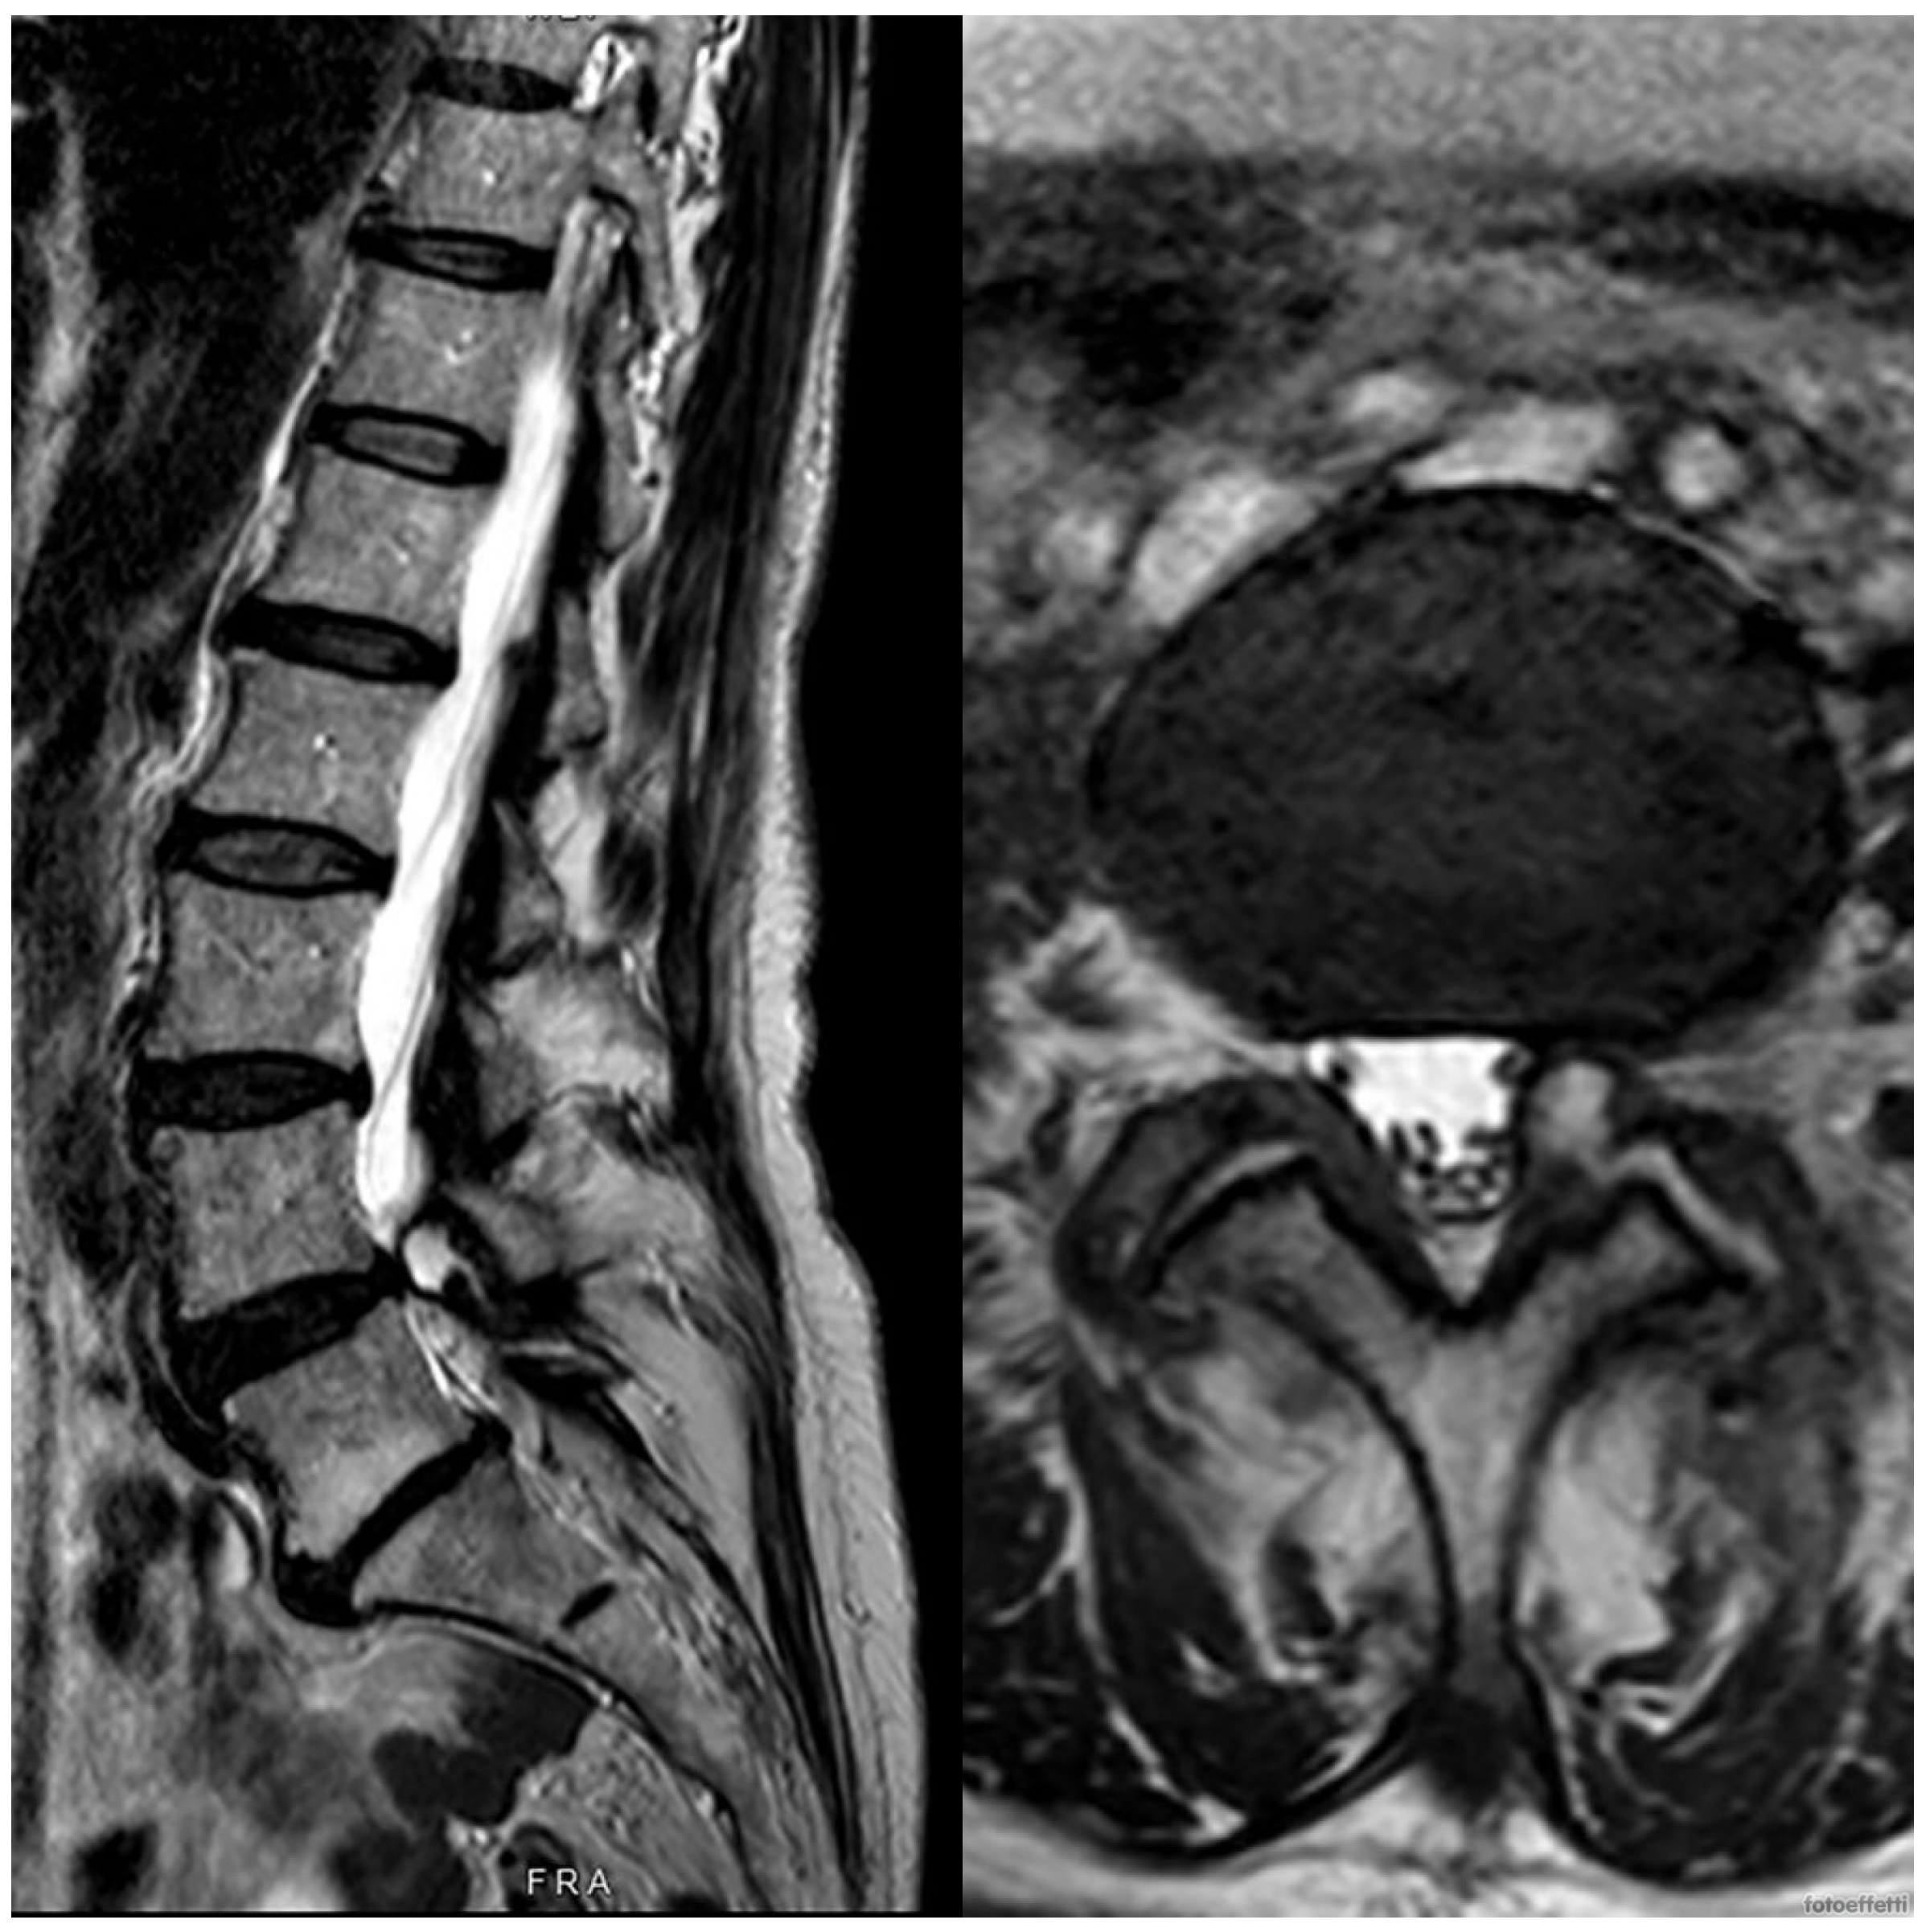

2. Case Presentation